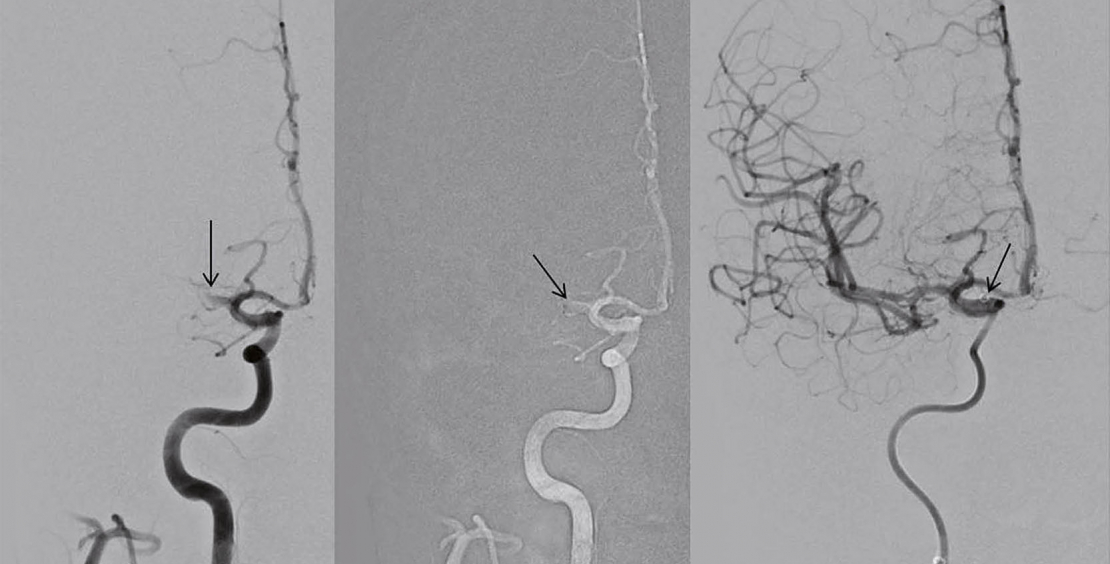

Ob Patienten mit kleineren Gefässverschlüssen (Truncus superior oder inferior der Arteria cerebri media, Arteria cerebri anterior oder posterior) und schwerwiegender Symptomatik wie Hemiparese, Aphasie, Hemianopsie oder Neglect von einer endovaskulären Intervention profitieren, ist nicht eindeutig geklärt. Kleinere Stentretriever und Aspirationskatheter werden entwickelt, um peripher gelegene Verschlüsse zu erreichen. Retrospektiv analysierte Daten zeigen die technische Machbarkeit der endovaskulären Therapie mit guten Rekanalisationsraten bis 83% bei einem zerebralen Blutungsrisiko von 7%. Ein funktionell gutes Ergebnis (mRS 0-2) erreichten jedoch nur 30% der Patienten (8).